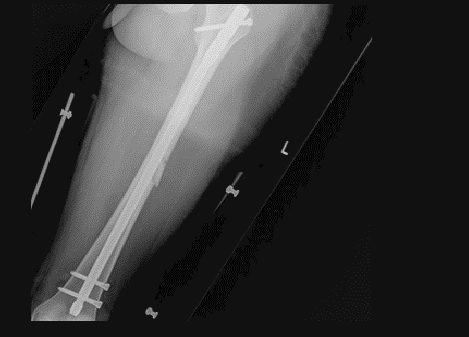

Fig6. - Midshaft tibia fracture.

Fig6. - Treated with an intramedullary nail